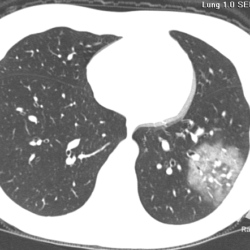

Os agentes etiológicos infecciosos são variados (bactérias, vírus, fungos, parasitas…), mas o que ocorre nos pulmões durante uma infecção por qualquer tipo de agente é a substituição do ar alveolar por secreção (pus, muco, eventualmente sangue ou necrose…) e com isso a manifestação radiográfica vai ser a mesma já que todas estas secreções apresentam a mesma densidade radiográfica: partes moles.

E o nome dado a esta alteração radiográfica que corresponde à substituição do ar alveolar por líquido é a consolidação alveolar.

Uma consolidação alveolar é, por definição, uma opacidade (imagem densa, branquinha) homogênea ou às vezes heterogênea (pela presença de calcificações ou cavidades), de limites mal definidos, exceto quando toca a pleura da parede ou das cissuras pulmonares. É um termo usado tanto em radiografia, como em tomografia computadorizada. Na tomografia, um outro termo é usado: vidro fosco, que é uma opacidade (branquinha mas não tanto como a consolidação), que borra o pulmão mas deixa ver os vasos de permeio (igual bigode de adolescente: dá pra ver todo o fundo).

Nós vamos mostrar aqui um pequeno apanhado de pneumonias de variados agentes, em diversos segmentos e lobos pulmonares, com extensões variadas. O objetivo é identificar o padrão radiológico de consolidação alveolar e não determinar o agente infeccioso, isso vai ser assunto para mais adiante. Aliás já antecipo que é fundamental saber localizar a lesão, porque alguns destes bichos gostam de determinados segmentos, alguns tumores também têm as suas preferências, então localização é fundamental. Se localização não fosse importante, um apartamento na beira do mar sairia o mesmo preço de um apartamento de frente pra BR-101, concordam?